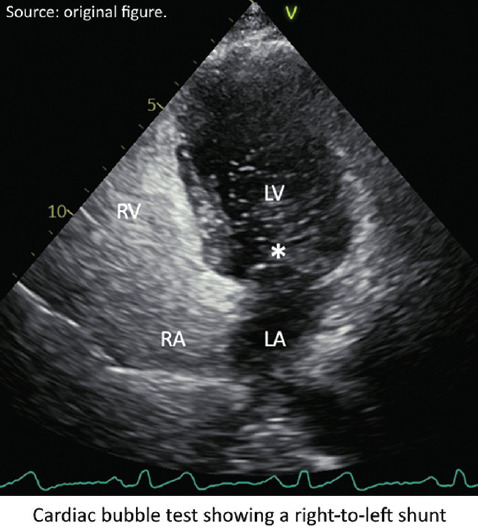

大约25%-40%的缺血性中风是隐源性的,尽管进行了彻底的评估,但仍无法确定病因。隐源性中风背后的机制通常是栓塞性的,经常起源于隐匿的心脏来源。无顶冠状窦(UCS)是一种罕见的先天性异常,涉及冠状窦顶部部分或完全缺失,导致左心房和冠状窦之间的连接。这种缺陷可以是无症状的,也可以表现为分流引起的矛盾栓塞等症状。我们报告一位70岁男性患者,有长期胸痛和神经系统症状史,后来通过心脏计算机断层扫描(CCT)诊断为UCS (III型和IV型)。心泡试验证实右至左分流,经胸超声心动图未发现。该病例强调了在诊断隐源性卒中时考虑先进成像技术(如CCT)的重要性,因为超声心动图可能由于心脏后部结构的可视性差而遗漏缺陷。

Around 25%-40% of ischemic strokes are cryptogenic, with no identifiable cause despite thorough evaluation. The mechanisms behind cryptogenic strokes are often embolic, frequently originating from occult cardiac sources. An unroofed coronary sinus (UCS), a rare congenital anomaly, involves a partial or complete absence of the coronary sinus roof, leading to a connection between the left atrium and the coronary sinus. This defect can be asymptomatic or present with symptoms such as paradoxical embolism due to shunting. We present the case of a 70-year-old male with prolonged chest pain and a history of neurological symptoms, who was later diagnosed with a UCS (types III and IV) through cardiac computed tomography (CCT). A cardiac bubble test confirmed a right-to-left shunt, which was not detected on transthoracic echocardiography. This case underscores the importance of considering advanced imaging techniques such as CCT in the diagnosis of cryptogenic stroke, as echocardiography may miss defects due to poor visualization of posterior cardiac structures.